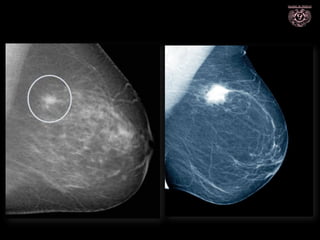

MAMOGRAFÍA

• Ha disminuido la mortalidad entre el 26-39%

• En toda mujer >40 años, anual

• Cada 2 años en >50 años

• En mujeres con antecedentes de riesgo elevados, 30 años

• Salen del tamizaje Mujeres >74 años con 2 exámenes previos

negativos

Puntaje BI-RADS

Benigno: >98% casos

Maligno: >95% casos